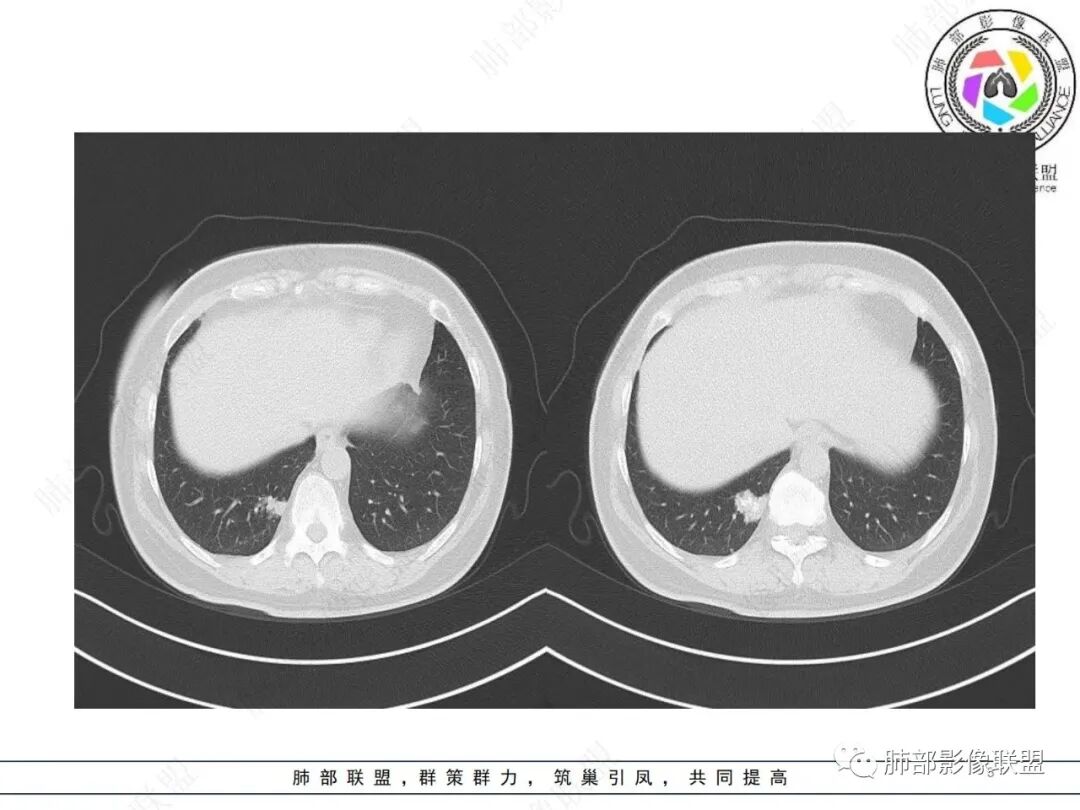

中年女性,右肺下叶后基底段胸膜下不规则稍低密度结节影,内见多发钙化,边缘部分平直,邻近胸膜下脂肪间隙清晰,增强扫描呈均匀轻中度强化,病灶边缘见少许小斑片状影,考虑良性病变,炎性肉芽肿可能,鉴别错构瘤

右肺下叶后基底段结节,形态不规则,有分叶和毛刺,内可见爆米花样钙化,实性成分有强化,绿色无坑肯定考虑错构瘤,晨读估计不会这么简单,所以考虑腺癌?转移性腺癌?鉴别结核

右肺下叶胸膜下不规则结节,分叶,其内爆米花样钙化,轻度强化,考虑错构瘤,鉴别腺癌

中年女性,无临床症状,胸部CT右肺下叶基底段实变影,边缘清楚,部分边缘刀切征,中间大部分钙化,局部胸膜无侵犯,似乎可见支气管充气征,考虑炎性肉芽肿,错构瘤待排

这个形态还是像腺癌,有膨隆有分叶,边缘磨玻璃边界清,非钙化部分轻度强化。腺癌可以钙化的,估计是干扰项

右肺下叶分叶状实性结节伴钙化,胸膜牵拉似有侵犯,增强后轻度强化,倾向恶性,腺癌可能。

右肺结节,边界清楚,中心钙化,钙化边缘模糊,轻度强化,考虑腺癌,鉴别错构瘤。

右肺下叶内基底段胸膜下分叶状肿块,边界清,密度不均匀,有成簇状钙化(与错构瘤钙化不同),实性部分有强化,肿块边缘凹陷明显(有收缩力),周围集血管束特点,方向首选肺肿瘤,考虑肺腺Ca。